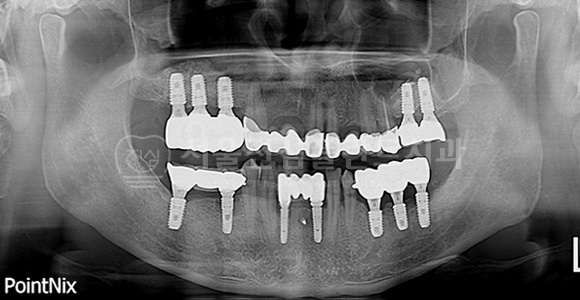

전체 임플란트

-

BEFORE

AFTER

발치즉시 임플란트 + 전체 임플란트 + 즉시 부하